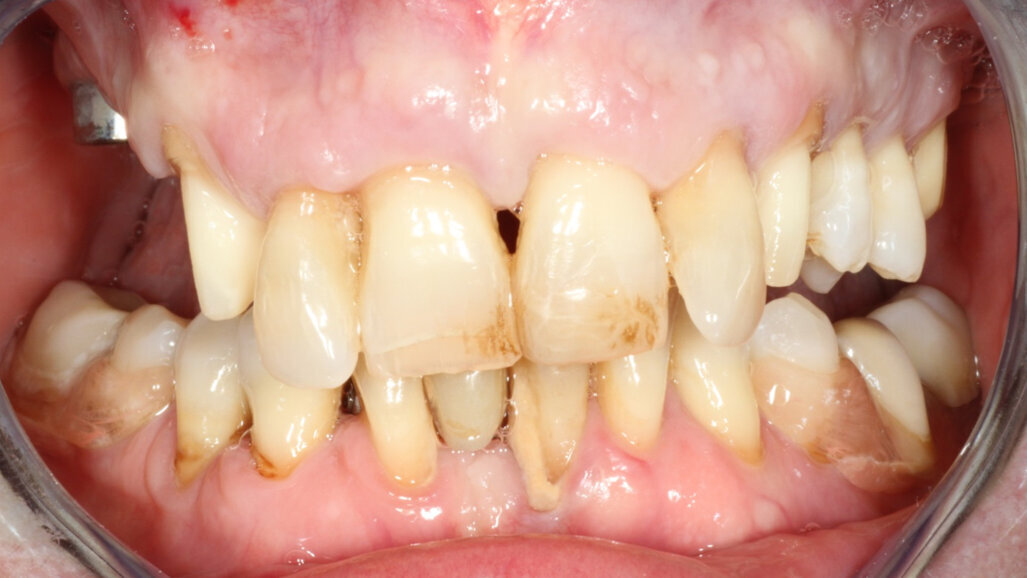

The 58-year-old, non-smoking and systemically healthy female patient was referred by her dentist to our dental clinic for implant treatment. The patient’s main complaints were poor aesthetics in the upper jaw, including a high smile line and distinct tooth pattern anomalies in the anterior maxilla (Figs. 1 & 2), as well as masticatory discomfort. Teeth #17, 15 and 27 were missing and had not undergone any prosthetic treatment, whereas the five missing teeth in the premolar and molar areas on both sides of the mandible had been replaced with a removable partial denture. All remaining teeth were affected by Stage IV periodontitis according to the 2017 Classification of Periodontal and Peri‐implant Diseases and Conditions, displaying a mean periodontal pocket depth of 5.6 mm.7 Mean bleeding on probing and mean plaque index were 70% and 80%, respectively. With respect to periodontal parameters, as well as to oral hygiene measures (visible calculus and dental plaque), the patient’s oral hygiene was graded as poor. The patient had been treated elsewhere with two implants in the posterior maxilla in order to replace the right first premolar and first molar (Fig. 3). She had a thick flat biotype, according to a definition introduced in 1977.8, 9